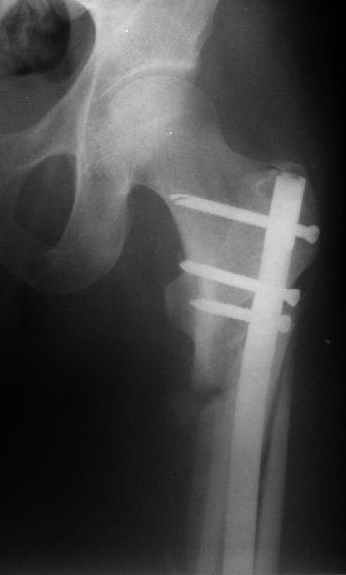

Могу скромно напомнить о существовании стержня нашей модификации.

В частности, на проксимальном конце сделано еще одно дополнительное статическое отверстие. Можно ввести в проксимальном отделе 4 винта, из них 3 статические (2 в круглые отверстия и 1 по нижнему краю овального). Картинки в приложении. На дистальном конце стержня тоже кое-что улучшено. Спрашивайте в аптеках, как говорится. Выпускается предприятием "ЦИТО" (Москва), то есть это малобюджетное решение.

Конечно, мы не синтезируем остеопорозые вертельные переломы согласно прилагаемому примеру, винты 6 мм вырежутся. Но у более молодых при хорошем качестве кости такие или подобные гвозди с поперечным расположением винтов вполне применимы для меж- и подвертельных переломов.

Это было года 2,5 назад, мы тогда еще уточняли возможности шинирования с угловой стабильностью гвоздем с поперечным расположением винтов при переломах проксимального отдела бедра. Пациенту не пришлось приобретать намного более дорогой рекон или проксимальный гвоздь. В приложении еще несколько примеров применения того гвоздя при высоких переломах бедра, в том числе с более латеральной точкой входа. Гвоздь изгибаем для этого.